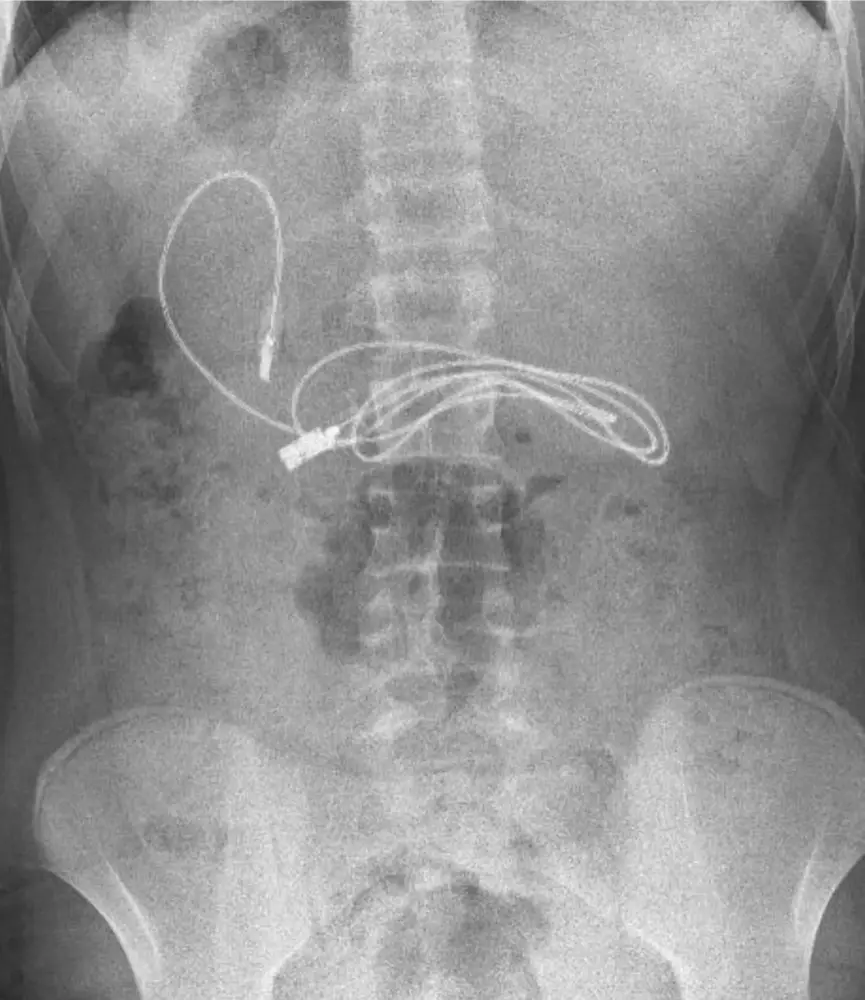

À Diyarbakir, dans le sud-est de la Turquie, des médecins ont du retirer un câble de USB 2.0 Micro USB de 90cm long de l’estomac d’un garçon âgé de 15 ans après qu’il ait commencé à se plaindre de nausées et de douleurs.

Après avoir effectué un radio, des médecins ont découvert le câble enroulé à l’intérieur de son estomac mais n’étant pas équipé, il ont immédiatement transféré à l’hôpital universitaire de Firat à Elazig, qui se trouvait à deux à trois heures de route.

À son arrivée, le professeur Yasar Dogan, chef du département de gastroentérologie, d’hépatologie et de nutrition pédiatrique, et son équipe ont retiré de le câble par endoscopie.

Le professeur Yasar Dogan a déclaré : « Nous avons évidemment eu du mal à retirer le câble, car une extrémité du câble était passée dans l’intestin grêle. Après la fin de l’intervention, le patient a été renvoyé chez lui en bonne santé. »